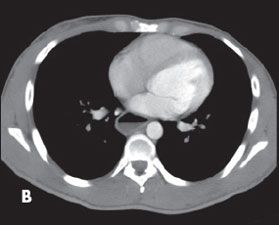

Esophagogastroduodenoscopy revealed a mildly dilated lower third of the esophagus (A). CT demonstrated a dilated esophagus (B). A barium swallow showed the classic “bird’s beak” appearance of the distal esophagus with proximal esophageal dilatation (C and D). A diagnosis of achalasia was made.